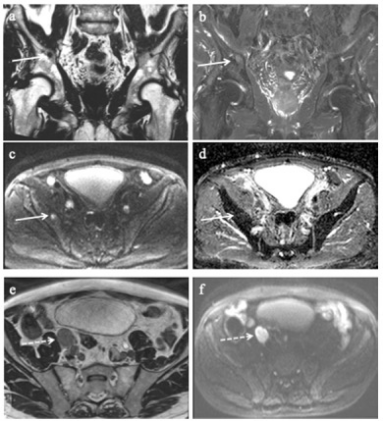

圖 一名82歲患者,cT3/radT4,PSA 108 ng/ml,ISUP 5。實線箭頭表示右側坐骨體轉移,點狀箭頭表示區域淋巴結轉移。a 冠狀 T2 dixon 脂相、(b) 冠狀T2 dixon 水相、(c) 軸位 DWI b800 s/mm2,(d) 軸位 ADC 圖,(e) 軸位 3DT2,(f) 軸位 DWI b800 s/mm2

本研究納入了390名患者,其中68%為高危患者,32%為不利的中危患者。在高危組中,區域性和非區域性淋巴結轉移率分別為11%和6%,骨轉移率為10%。在不利的中危組中,區域性和非區域性淋巴結轉移率分別為4%和0.8%,骨轉移率為0.8%。在所有患者中,0.5%的轉移僅發生在腰椎,4%發生在骨盆,3%發生在骨盆和腰椎。所有骨轉移患者都有 radT3-4,而radT3-4患者的淋巴結轉移風險增加了4倍(OR 4.48,95% CI:2.1-9.5)。